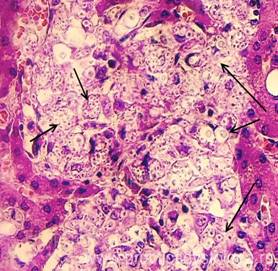

Рис. 3. Септический метастатический очаг острого гнойного межуточного миокардита с колониями бактерий. В окружающем миокарде обилие сливающихся друг с другом мелких очагов умеренной-выраженной фуксинофилии цитоплазмы кардиомиоцитов в виде мелких их участков, окрашенных в красный цвет на жёлто-зелёном фоне. Окраска: ГОФП-метод (по Ли). Увеличение х100, х250.